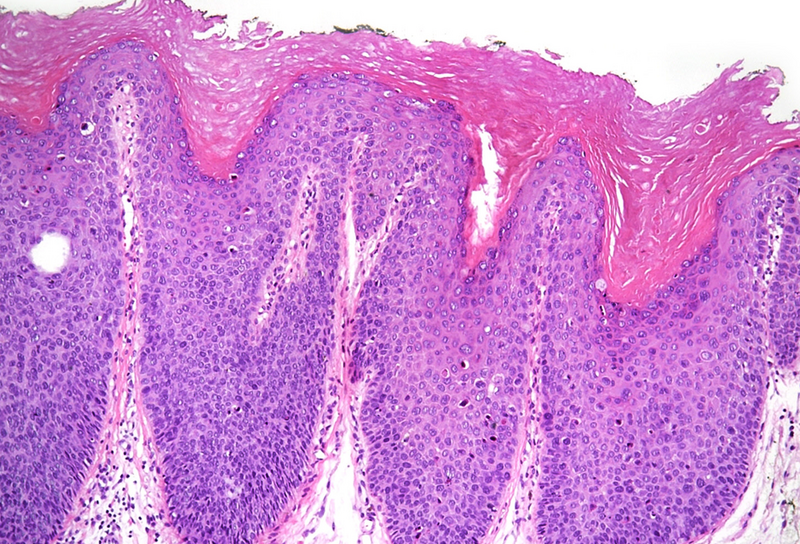

Microscopic examination revealed squamous dysplasia, affecting the full thickness of the epithelium (Panel A), with eventual koilocytes and increased apoptosis (Panel B). Mitotic figures were found throughout the epithelium, with marked increase in Ki-67 staining (Panel C). P16 immunohistochemistry reaction showed diffuse, block positivity which reached the excision margin (Panel D).

Histologically, cytological and architectural atypia is visible is at least half of the thickness of the epithelium. Koilocytes may be present, as well. Mitotic figures may often be found in the upper half of the epithelium. Diffuse, block positivity of p16 may reflect HPV genome internalization, however, the definitive diagnostic tool of identification is polymerase chain reaction (PCR). Regarding differential diagnosis, several reactive epithelial changes, and metaplasias may mimic HSIL, especially on small biopsy samples. In such cases, p16 may play even more crucial role. Naturally, invasion has to be ruled out in each case.